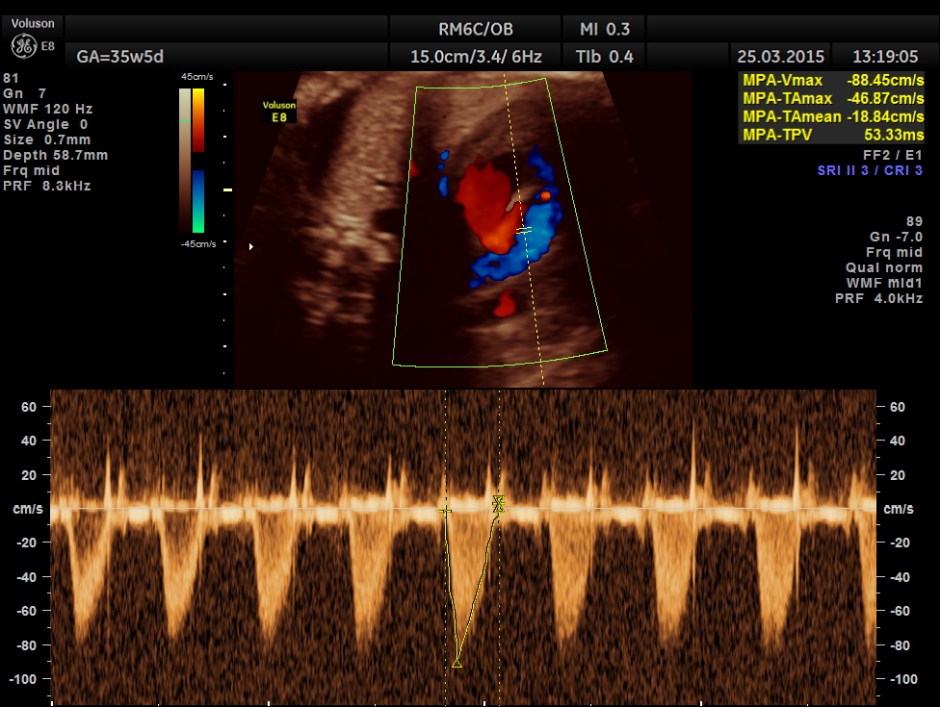

Mitral valve doppler flow.